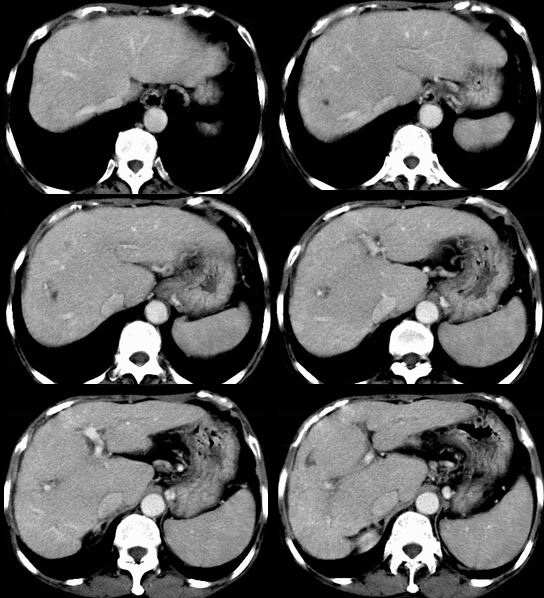

患者,女,53岁。恶心、上腹痛、下腹胀、消瘦2月余。曾有肝硬化、乙肝、胆囊炎病史。

b超发现肝右叶实质性占位,做ct检查。

动脉期

此病灶不具备典型小肝癌的强化方式,从动脉期及静脉期看病灶是呈逐渐强化。

结合病史及b超表现,考虑肝癌合并脂肪变性可能大。平扫病灶密度较一般常见肝癌密度偏低,增强动脉期强化不明显,但长期的肝炎及肝硬化病史,不能不考虑肝癌的可能性,合并脂肪变性,病灶强化的程度就会明显减低。建议必要时mri三期增强扫描。

动脉期无增强,静脉期可见部分增强,考虑肝内胆管细胞癌,